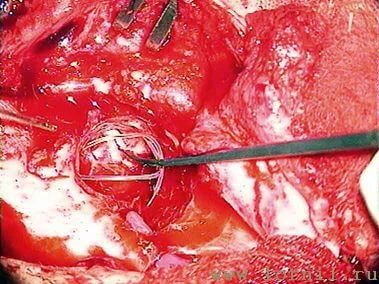

Затем борами подготавливали ложе, устанавливали и фиксировали в ложе имплант (рис. 9, 10). Соединительный кабель проводился через заднюю тимпаностому в барабанную полость.

У пациентов с аномалией развития уха и после радикальной операции катушка импланта была установлена в круглое окно (рис. 13, 15, 16). Для этого крепление катушки подворачивали (рис. 14). Далее укладывали фасцию височной мышцы в нишу окна улитки (рис. 15), затем на фасцию устанавливали катушку импланта и подворачивали края фасции. Фиксация конструкции обеспечивалась полоской аутохряща из ушной раковины пациентки (рис. 16).

Если пациенту ранее была выполнена тимпанопластика с оссикулопластикой частичным или полным титановым оссикулярным протезом катушка импланта может крепиться на ножке протеза (рис. 17, 18).